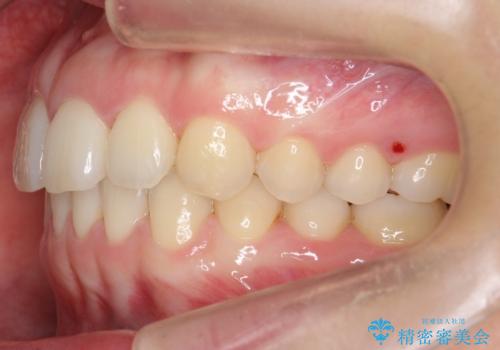

下の前歯が1本短い インビザラインと部分矯正の組み合わせ

- 前歯のガタつきと、下の前歯が一本短いことを主訴に来院。

インビザラインのマウスピースではめる装置で歯を引っ張り出すことは難しいと説明し、下の前歯だけワイヤー部分矯正を行ってからインビザライン矯正で仕上げをしました。